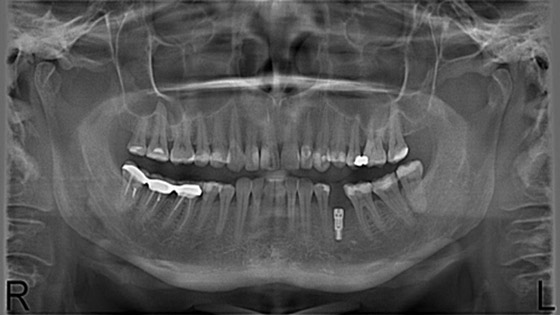

اكتشاف مذهل.. هناك علاقة بين اشعة فحص الاسنان وسرطان الدماغ!!

اكتشف علماء من جامعة ييل الأمريكية، خلال دراسة علمية، ان الأشخاص الذين يعانون من سرطان الدماغ تعرضوا أكثر من غيرهم الى الأشعة السينية خلال مراجعتهم أطباء الأسنان لمعالجة اسنانهم. وأكثر من هذا تبين ان الرجال والنساء الذين يعانون من سرطان الدماغ، تعرضوا عند مراجعتهم أطباء الأسنان الى الأشعة السينية أكثر من مرة لتحديد مدى تسوس الأسنان التي تحتاج الى العلاج.

جرت هذه الدراسة الفريدة تحت اشراف البروفيسورة اليزابيث كلاوس، حيث خضع لها 1443 شخصا اعمارهم بين 20 و79 سنة جميعهم يعانون من ورم سحائي " Meningioma "، كما خضع للدراسة 1350 شخصا سليما. بينت نتائج هذه الدراسة ان الذين يعانون من الأورام السرطانية في الدماغ خضعوا لفحص الأسنان بالأشعة ضعف أو أكثر من الأصحاء، وأن المرضى الذين خضعوا لفحص تجويف الفم بالأشعة ارتفع احتمال اصابتهم بسرطان الدماغ بمقدار ثلاثة أضعاف.

وتشير البروفيسورة كلاوس، الى أن أجهزة الأشعة المستخدمة حاليا في المستشفيات لا تسبب أضرارا كالأجهزة السابقة، ومع ذلك ينصح الأطباء بعدم التعرض الى الأشعة مرات متكررة خلال فترة زمنية قصيرة.